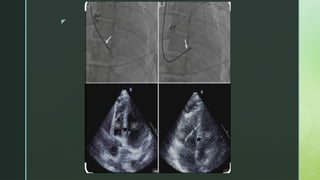

IMAGING GUIDANCE

 EMB is mostly performed under fluoroscopic guidance.

 Pre procedural imaging like echo, cardiac MRI, PET can be used to direct

site specific EMB

 Procedural imaging like echocardiography can be performed simultaneously

with fluoroscopy to improve the accuracy of the EMB procedure.

 Intracardiac echo has also been successfully used to guide EMB of cardiac

tumours.

 Electroanatomic voltage mapping is being used in diseases with focal

pattern associated with VT ( sarcoidosis ), it is further facilitated with 3 D

mapping.